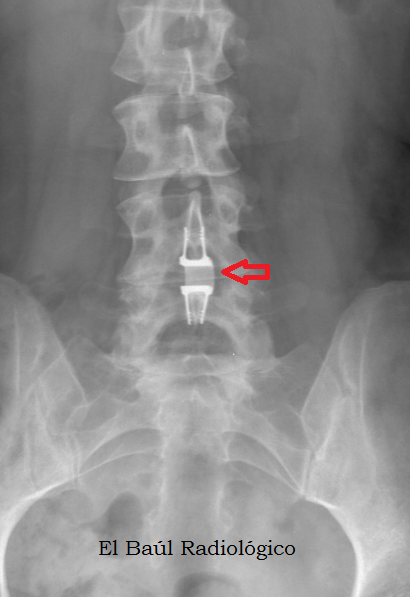

A) DISPOSITIVO INTERESPINOSO (BIOMET)

Protesis+1.png

FIGURA 1-A) Dispositivo interespinoso colocado entre las apófisis espinosas de L4 y L5. Cuando lo vemos por primera vez, en una radiografía simple, no podemos dejar de pensar ¿Será una hebilla del pantalón?

(Interspinous device placed between the spinous apophyses of L4 and L5.When we first see it, in a plain film, we can not stop thinking about. Will this be a buckle of the pants? ).